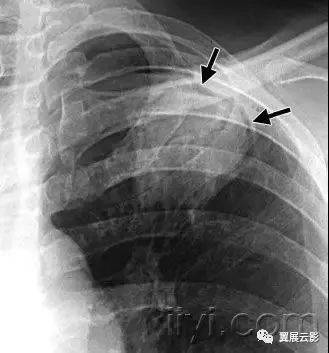

六、顶冠或肺尖帽

病理:是肺尖的帽状病变,常由肺内或者胸膜的纤维化,向下牵拉胸膜外脂肪,也可能是慢性缺血导致脏层胸膜的透明斑形成所致。随年龄增长,发病率增加。主动脉撕裂导致的血肿,或者炎症或者肿瘤,导致液体积聚在胸膜腔或者壁层胸膜外,也可以出现此征象。

平片和CT:常见表现是均匀的软组织密度,位于单侧或者双侧肺尖之上呈帽状,下界尖锐且不规则。厚度可变,甚至可达30mm。有时候在横断CT上,肺尖帽可以类似肺尖的实变。